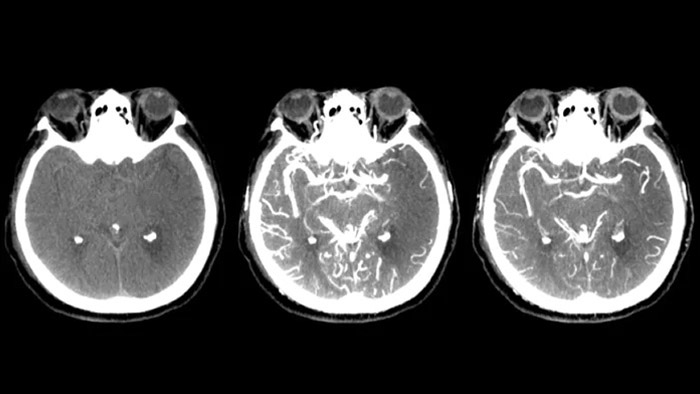

Tres SmartCT

Visualización similar a una TC

SmartCT Soft Tissue  genera una visualización de los tejidos blandos similar a la de una TC y apoya el diagnóstico del accidente cerebrovascular de tres maneras. Una exploración sin contraste ayuda a detectar los cambios isquémicos tempranos. Una exploración de fase temprana ayuda a identificar la oclusión proximal. Una exploración con contraste de fase tardía ayuda a detectar colaterales.

Ver llenado colateral

Visualización del llenado colateral

La vista dual para ver los volúmenes de TC de haz cónico de fase temprana y tardía uno al lado del otro mejora la identificación de la penumbra y permite la visualización del relleno colateral.